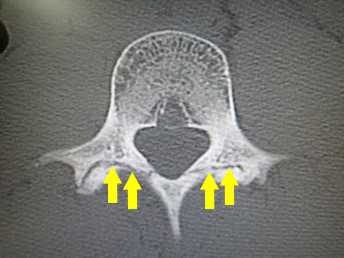

せぼね(脊椎)は7個の頚椎、12個の胸椎、5個の腰椎と仙椎から構成されます。腰椎は主に5つの骨と、間にあるクッションのような椎間板、また神経組織が通っている脊柱管から成り立っています。腰椎分離症とは、腰の骨の後ろの部分にある上・下関節突起間部と呼ばれる部分の連続性が断たれた状態を言います。上・下関節突起間部に疲労骨折が生じ、偽関節(骨がくっつかない)になると腰椎分離症となります。さらに、腰の骨が前方にすべってしまうと腰椎分離すべり症と呼ばれ、分離症患者の10~20%が分離すべり症に移行すると言われています。

せぼねの変形や椎間板の傷み具合、すべりや不安定性の有無、脊柱管の狭さ、またせぼね全体のバランスなどを見るためにX線検査やCT検査、MRI検査などを行います。進行例では脊柱管の狭さをより詳しく評価するために入院して脊髄造影検査や、同時にどの神経が痛みの原因となっているかを明らかにするために神経の枝に直接麻酔薬を注入する選択的神経根ブロックを行う場合があります。成人期では血管性の下肢の痛みがないか評価するために両手足の血圧を測ったり、骨粗鬆症の有無を評価するために骨密度検査を行うこともあります。